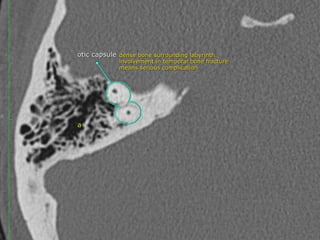

CT Temporal Bone Search Pattern with selected images :

Use both axial and coronal CT

images

Otic capsule:

•Superior semicircular canal (SCC)

•Posterior SCC (P)

•Lateral SCC (L)

•Vestibule (v)

•Aditus ad antrum (A)

•Cochlea

•Modiolus (mo)

•Basal turn (b)

•Middle turn (m)

•Apical turn

•IAC

•Facial n.

•labyrinthine segment (Fnl)

•geniculate segment

•tympanic segment

•Vestibular aqueduct